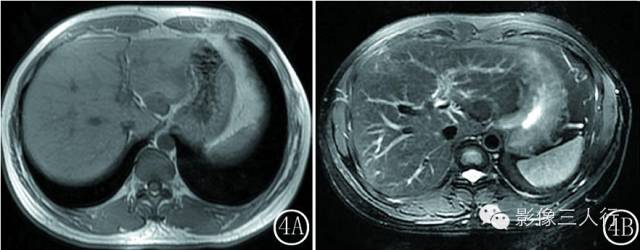

图 4 MRI 全瘤强化型 IPL 。 图 4A T 1WI ,病灶呈均匀低信号 。 图 4B T 2WI ,病灶呈低信号 。 图 4C 门脉期 ,病灶内见分隔状强化 。 图 4D延迟期 ,病灶持续强化 ,呈全瘤强化 ,中心见少许低信号不强化区